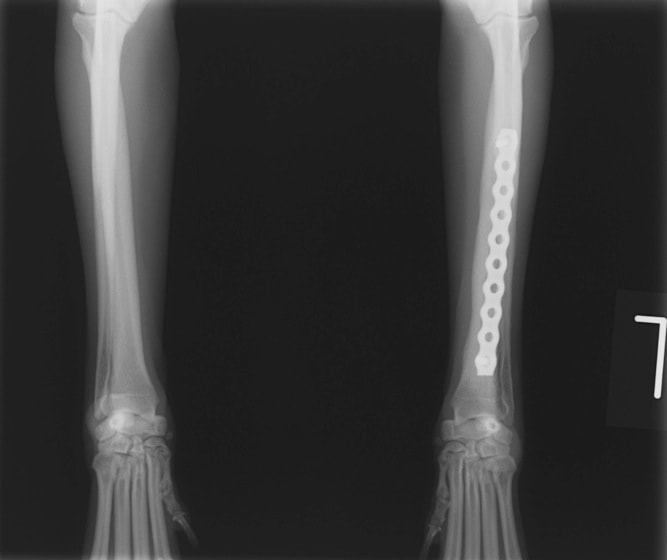

Advanced Locking plate system と Locking compression plate system

当院ではAdvanced Locking plate system(ALPS)と、Locking compression plate system(LCPS)という骨接合法で骨折症例の治療を行っています。

Advanced Locking Plate System

従来型のプレートのように広い面積で骨と接するプレートを用いて固定を行った場合、プレート下の骨はプレートとの接触面において血行が絶たれ壊死し、それがリモデリングされると骨密度が低下する。この骨密度の低下防ぐために、骨折部局所への血行を温存することの重要性が近年改めて認識されるようになってきている。Advaed Locking Plate System (ALPS)は従来型のプレートシステムの欠点を改良し、より使いやすく、より骨への血行を阻害しないようにというコンセプトで作られた。

トイプードル 右遠位橈尺骨短斜骨折のALPSによる内固定

Locking Compression Plate

LCPは、スクリュー(ネジ)とプレート(金属の板)をロックする特殊な構造により骨折部位を固定する新しい世代のプレートシステムです。ひとつのホールでロッキングスクリューとスタンダードスクリューの使用を選択できるユニークな構造をしているため、骨折断端間の圧迫を目的とした従来型プレート固定法に加え、高い角度安定性を有するロッキングスクリューを用いた固定法の選択が可能です。従来のプレートシステムでは困難だった部分の骨折や癒合不全の症例に高い治療効果をもたらします。